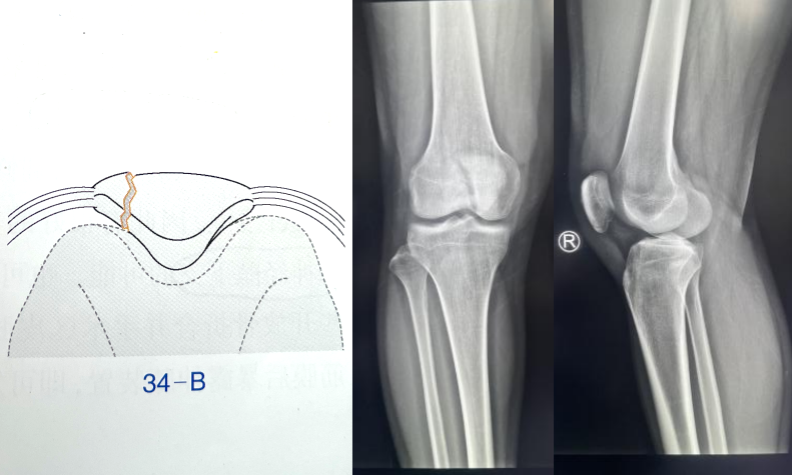

髌骨骨折只占全身骨折的 1%,治疗方式的选择和并发症的防治尤其要注意,急诊来了髌骨骨折患者,你怎么处理?髌骨是人体最大的籽骨,位于膝关节伸膝装置内。解剖特点包括近端宽大的基底和关节外的远侧尖端,前面位于关节外,后面为关节面。股直肌和股中间肌止于髌骨基底部,股内侧肌和股外侧肌止于髌骨的两侧。髌腱起于髌骨尖端,止于胫骨结节。髌骨骨折约占所有骨折的 1%,主要由直接暴力造成,如跌倒时跪地或膝关节屈曲时受到打击。典型的体征包括关节肿胀、压痛、伸膝功能部分或完全丧失。除以主诉和典型体征外,膝关节 X 线片也是必不可少的一项辅助检查,以膝关节正侧位 X 线片最常见,如果怀疑纵向骨折,膝关节屈曲 45° 时髌骨 30° 切位片可以辅助诊断。对于骨折不愈合、畸形愈合所致的关节面不平整以及髌股关节对应关系不良可采用 CT 检查。MRI 有助于诊断软骨缺损和损伤。34-B 型(部分关节内骨折,伸膝装置完整,如纵行骨折)髌骨下极骨折袢钢板结合克氏针、张力带固定 图源:作者提供

拉力螺钉加张力带钢丝固定或经胫骨结节绕髌环扎;经骨缝合撕裂的肌腱加髌骨和胫骨结节间钢丝环绕以加固缝合;袢钢板固定。无移位采用非手术治疗;移位并且单纯骨折采用横向拉力螺钉固定,骨质疏松患者需加环扎固定;对于多骨折块(星状)则采用髌骨环扎加张力带进行固定。克氏针加张力带钢丝;有第三个骨折块则采用拉力螺钉或克氏针加张力带钢丝固定;对于 4 个或 4 个以上的骨折块采用克氏针加螺钉加张力带钢丝进行固定;对于严重粉碎和软骨面广泛破坏的髌骨骨折,髌骨部分或完全切除也是一种可行的办法。